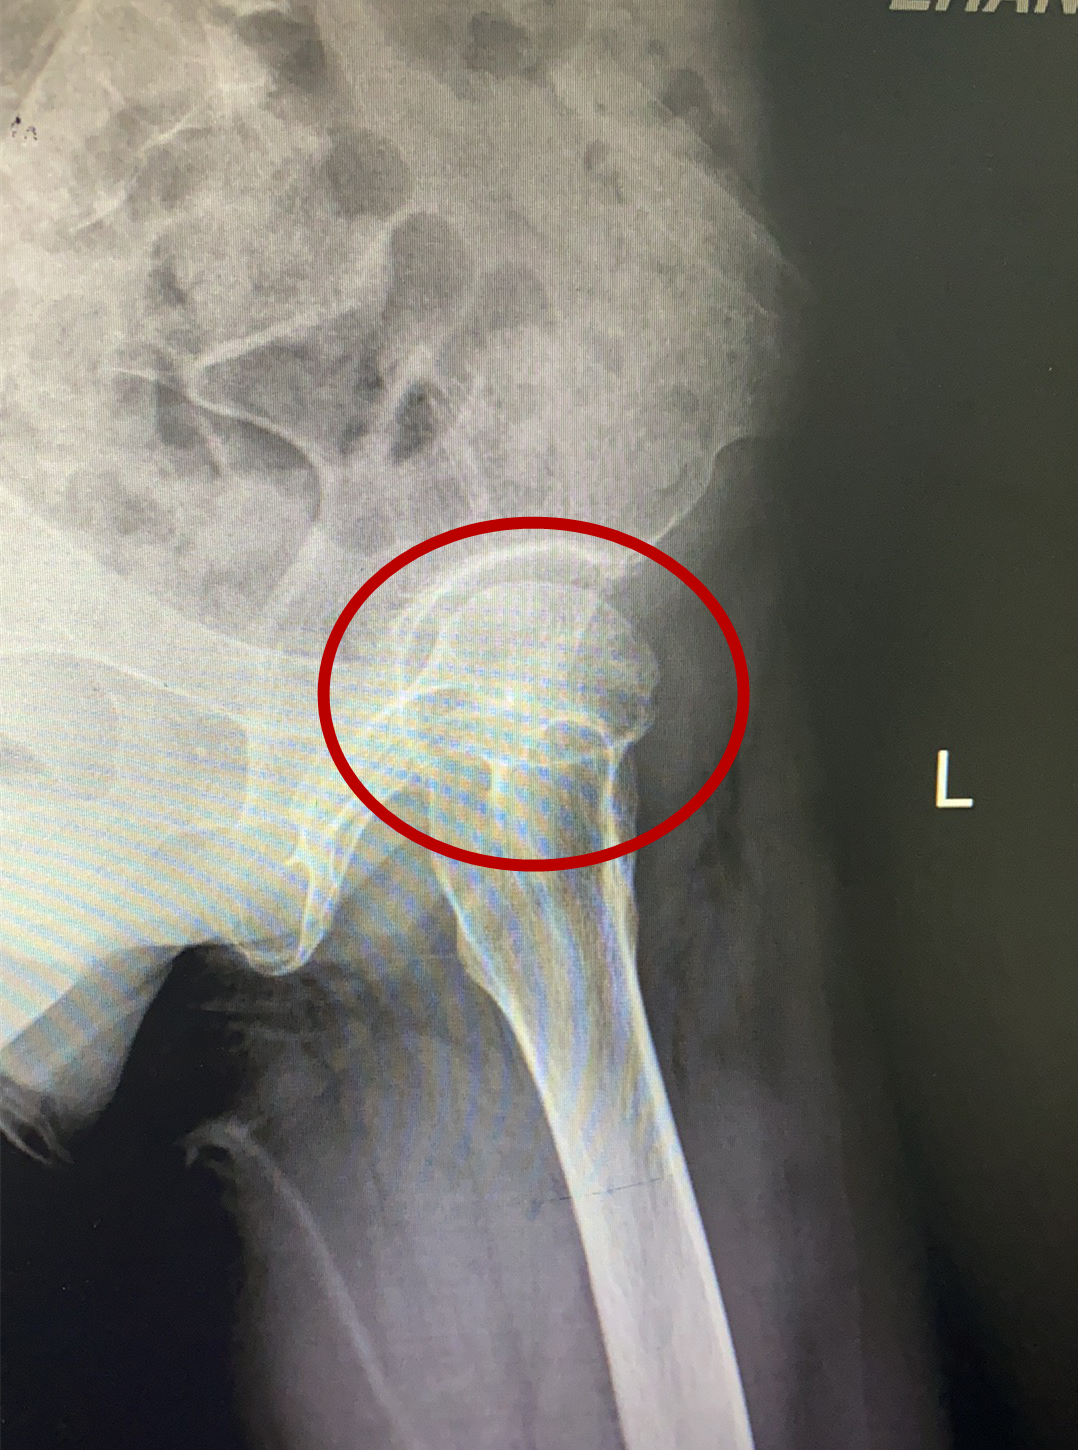

骨關(guān)節(jié)專家林石明副院長及其醫(yī)療小組成員,經(jīng)過反復(fù)研究患者的核磁共振及CT三維血管重建等資料后,考慮為左側(cè)股骨頭壞死,程度在二期到三期之間,具有“帶血管蒂腓骨骨移植”手術(shù)指征。目前國際上公認(rèn)“帶血管蒂骨移植”這項(xiàng)保髖技術(shù)成功率較高,但該手術(shù)技術(shù)難度較大,需要把小腿上約8cm腓骨連同臨近的腓骨動脈血管截一段下來,植入股骨頭頸的壞死區(qū)域,在顯微鏡下,將腓骨動脈與股骨頭臨近血管進(jìn)行對接縫合,重建血供讓壞死股骨頭獲得新生。該手術(shù)一旦成功,將為林女士保留住髖關(guān)節(jié)功能,能較快恢復(fù)日常勞動,且費(fèi)用較低。

術(shù)前影像